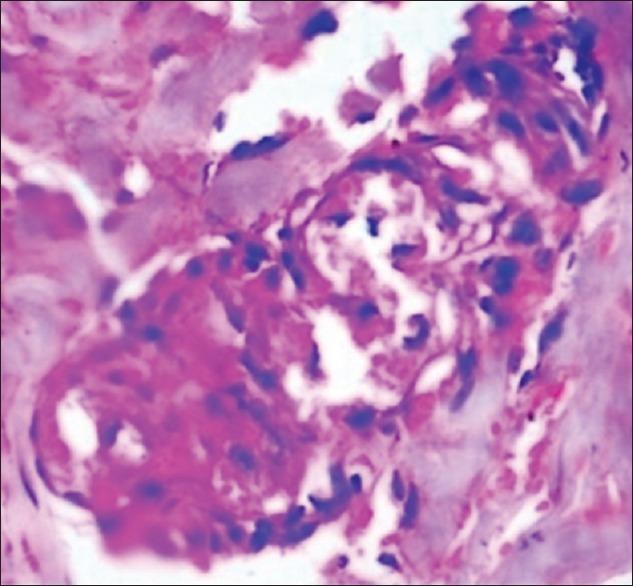

A 42-year-old male developed hemorrhagic bullae and erosions while in alcohol induced coma. The lesions were limited to areas of the body in prolonged contact with the ground in the comatose state. He developed rhabdomyolysis, progressing to acute renal failure (ARF). Histopathological examination of the skin showed spongiosis, intraepidermal vesicles, and necrosis of eccrine sweat glands with denudation of secretory epithelial lining cells. With supportive treatment and hemodialysis, the patient recovered in 3 weeks time. This is the first reported case of bullous lesions and sweat gland necrosis occurring in alcohol-induced coma complicated by rhabdomyolysis and ARF.

一名42岁男性在酒精性昏迷期间出现出血性大疱和糜烂。病变局限于昏迷状态下身体与地面长时间接触的部位。他发生了横纹肌溶解症,并进展为急性肾衰竭(ARF)。皮肤组织病理学检查显示有海绵形成、表皮内水疱以及小汗腺坏死,分泌上皮衬里细胞剥脱。经过支持治疗和血液透析,患者在3周后康复。这是首例报道的酒精性昏迷合并横纹肌溶解症和急性肾衰竭时出现大疱性病变及汗腺坏死的病例。